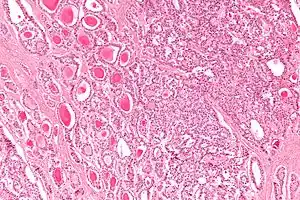

| Micrograph of a strumal carcinoid. H&E stain. | |

The strumal carcinoid is a type of monodermal teratoma with histomorphologic features of (1) the thyroid gland and (2) a neuroendocrine tumour (carcinoid).[1][2]